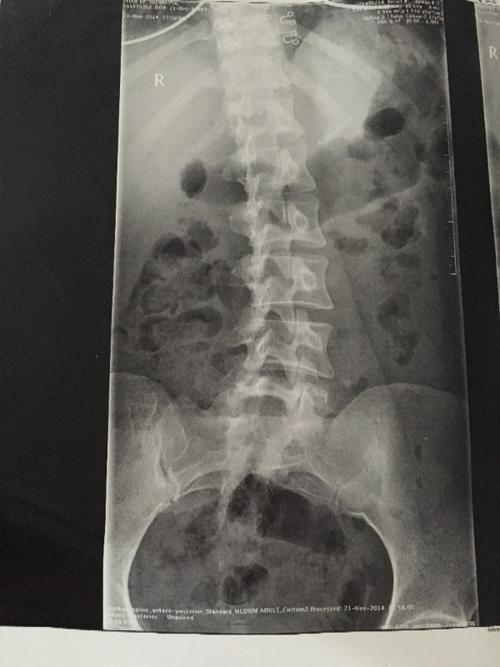

腰椎向左侧弯示意图

腰椎向左侧弯示意图,腰椎向左侧弯锻炼图

请问这是脊椎向左弯还是向右弯,,这个是腰椎放射x线.

我院腰椎正侧位及动力位x片显示,患者腰椎呈姿势性侧弯,退变明显,l4/5

髋关节活动受限,只能靠腰椎弯曲代偿